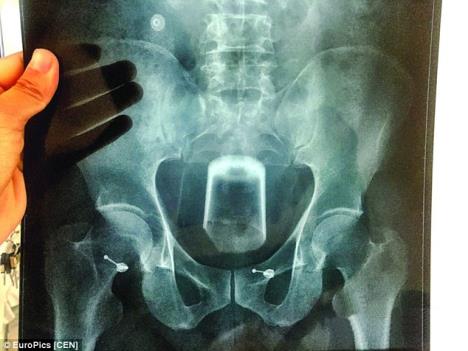

Reč je o posudi širokoj sedam centimetara koju je gurnuo u sopstveni rektum, što je prouzrokovalo velike bolove.

Ubrzo je shvatio da ga iz agonije mogu spasiti samo doktori. Tri hirurga iz Centralne bolnice Vuksi u istočnoj Kini udružili su snage kako bi uspeli da izbace čašu iz pacijentove zadnjice.

U drugoj bolnici uspeli su da izvade čašu. Tri hirurga zajedničkim snagama iz tri različita pravca, nakon jednosatne operacije uspeli su da izbace pomenuti sadržaj iz pacijentovog rektuma.

Pivska čaša se razbila čim su je izvadili. Doktor Li Čunvei istakao je da godišnje obave pet, šest sličnih operacija, a da se u telima ljudi znaju pronaći razne stvari, od patlidžana do drvenih šipki.